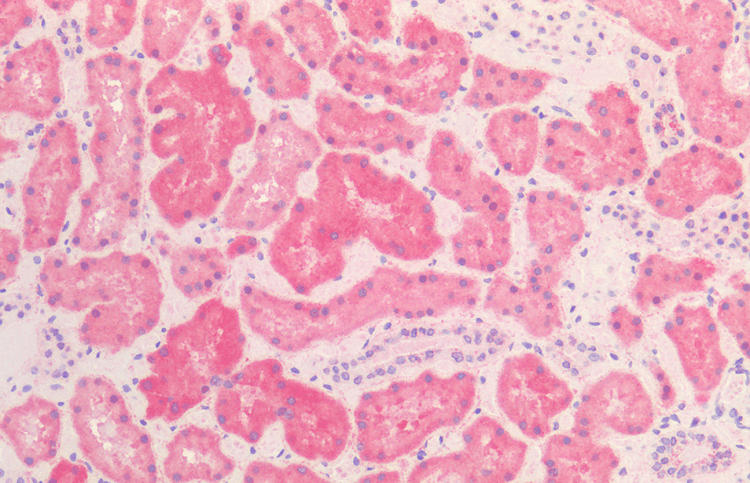

Mouse Monoclonal Hsp60 antibody. Suitable for WB, IHC-P and reacts with Human, Mouse samples. Cited in 6 publications. Immunogen corresponding to Recombinant Full Length Protein corresponding to Human HSPD1.

Applications IHC-P, WB